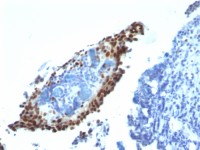

IHC-P analysis of human ovary, carcinoma tissue using GTX12571 GPR43 antibody.

Antigen retrieval : Heat-induced antigen retrieval